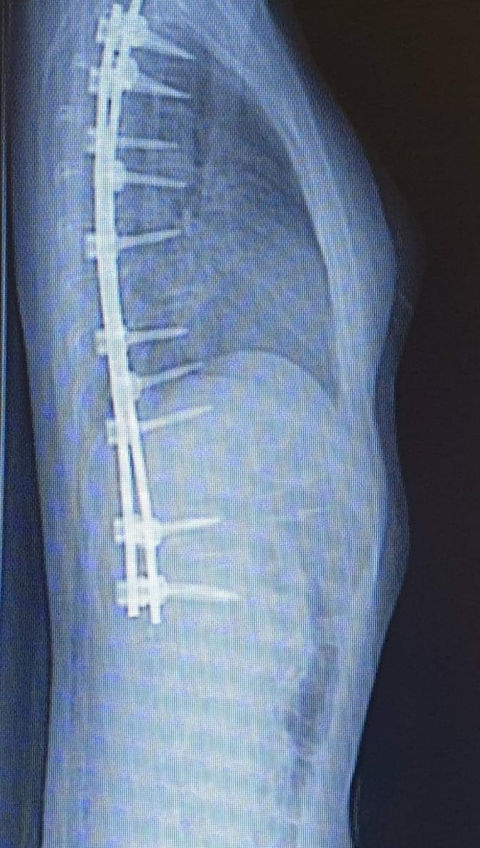

•Titanium alloy materials give an opaque image under

X-Ray, besides PEEK materials is able to be viewed transparently. This provides a more efficient

follow-up for the bone fusion through the implant material at post-operative period